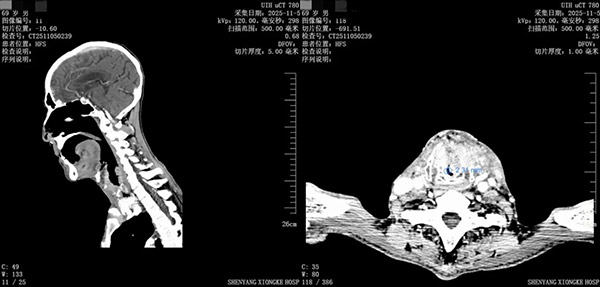

2025年11月6日上午,综合麻醉科王涛主任接到结核九病区任艳主任的紧急会诊通知,一名患者因颈部肿物压迫导致急性上呼吸道梗阻,患者喘憋明显,伴随剧烈呛咳及大量痰液,血氧难以维持,喉部气道最窄处不足3毫米,且合并一侧毁损肺既往史,生命危在旦夕。